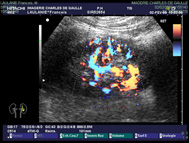

| ECHO-DOPPLER COULEUR |

Le doppler étudie l’écoulement du flux sanguin dans les artères et les veines. |

| La sonde placée sur la peau émet et reçoit le signal. La liberté du flux vasculaire ou son ralentissement voire son absence sont ainsi enregistrés. |

| L’utilisation du flux couleur permet aussi d’analyser

la circulation sanguine. |